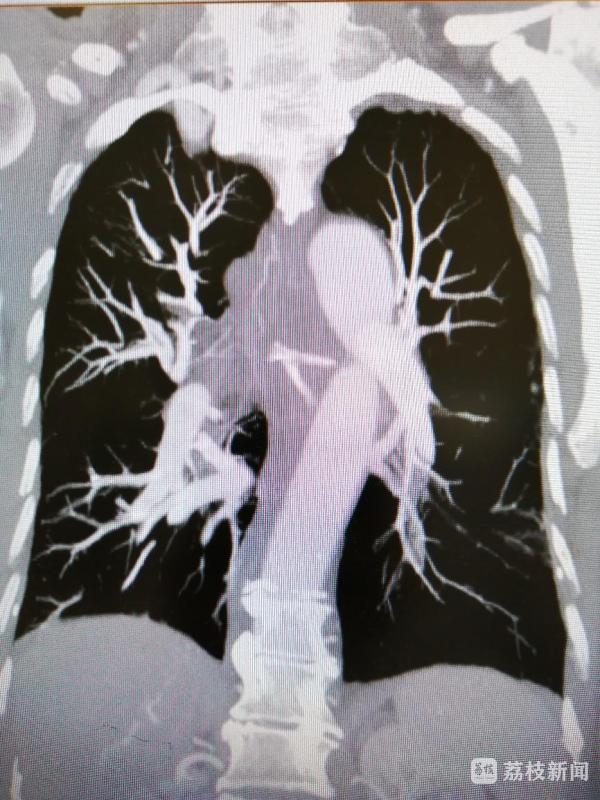

4天前,家住江苏睢宁的仝爷爷在吃了顿鸡肉后,感觉咽喉有异物感,于是便吞了一个饭团,希望将其咽下。然而3天后,异物感不仅没有消失,反而出现逐渐加重的胸前区疼痛,并伴随有吞咽困难、呼吸费力、发热等症状。在当地医院就诊后,被确诊为“食道异物并穿孔”,CT检查让人惊出一身冷汗:仝爷爷食道内的鸡骨呈树枝样Y型,竟像一把叉子一样牢牢卡在食道中段!因病情十分棘手,当地医院建议尽快转往大医院治疗,10月14日上午,已经被异物苦苦折磨多日的仝爷爷,在家属陪伴下来到江苏省人民医院急诊中心就诊。

患者病情紧急,“取骨”刻不容缓!急诊中心接诊后,第一时间联系到了消化内镜科刘莉副主任医师,刘莉副主任医师紧急安排进一步的胸主动脉CTA及三维重建检查,结果显示,患者病情不容乐观:鸡骨已卡在食道4天,所夹带的大量鸡肉、患者后续吞下的米饭已高度腐烂,局部炎症反应重,且已形成食道穿孔伴感染,术后极易发生并发症;患者77岁高龄并有强直性脊柱炎及脑梗病史;鸡骨紧邻降主动脉,一旦穿破大动脉,出血便会似“决堤”般,根本没有抢救机会!“针对患者的情况,开胸取骨的创伤和风险巨大,内镜取骨的手术难度和风险也很高,这就要求手术必须在几分钟之内完成,否则后果不堪设想”,刘主任说。